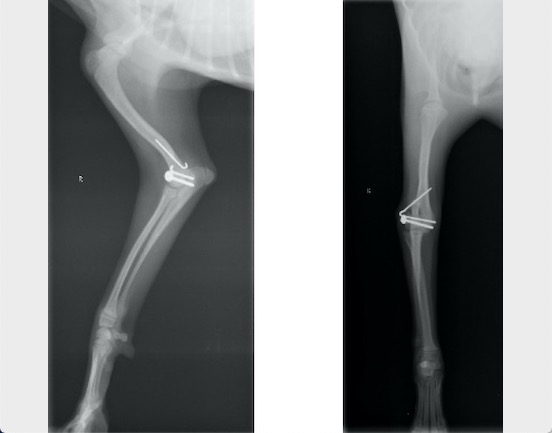

術中写真

皮質骨スクリューと2本のキルシュナーワイヤーにて固定しました